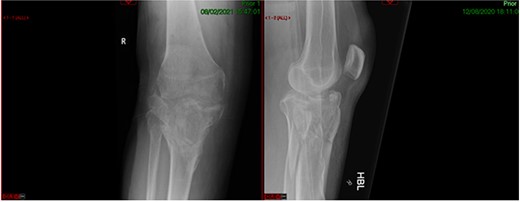

CASE 1

A 68-year-old gentleman who was diagnosed with a Schatzker type VI fracture having fallen 3 m from a ladder (Figs 1 and 2). The injury was closed and neurovascularly intact. The patient was monitored for signs of compartment syndrome. He rapidly developed significant fracture blisters that persisted for over 2 weeks despite regular dressing care. He was deemed too high risk for acute operative intervention because of a high risk of wound complications. Following a multidisciplinary team discussion, he was managed in a cast then a knee brace, mobilising non weight bearing for 12 weeks, at which point the fracture was seen to be healing in a valgus malalignment. The patient was allowed to partially weight bear and received physiotherapy. He was reviewed regularly until fracture had united (Fig. 3). At 8 months post-injury, the patient underwent total knee arthroplasty utilizing a Depuy Synthes (Warsaw, In) PFC Sigma TC3 tibial metaphyseal sleeve and stem, and femoral component without sleeve or stem (Fig. 4). The patient was reviewed post-operatively in clinic at 6 months, the wound had fully healed and the range of motion was 0°–120°. The patient’s pain was significantly reduced, and they were independently mobile. They were kept under annual review and seen at 5 years post-operatively with an Oxford Knee score of 35; the patient used no walking aids and was pain free at rest or during normal walking, with the radiograph demonstrating good osseointegration. The latest follow-up at 8 years revealed no radiographical change in implant (Fig. 5).